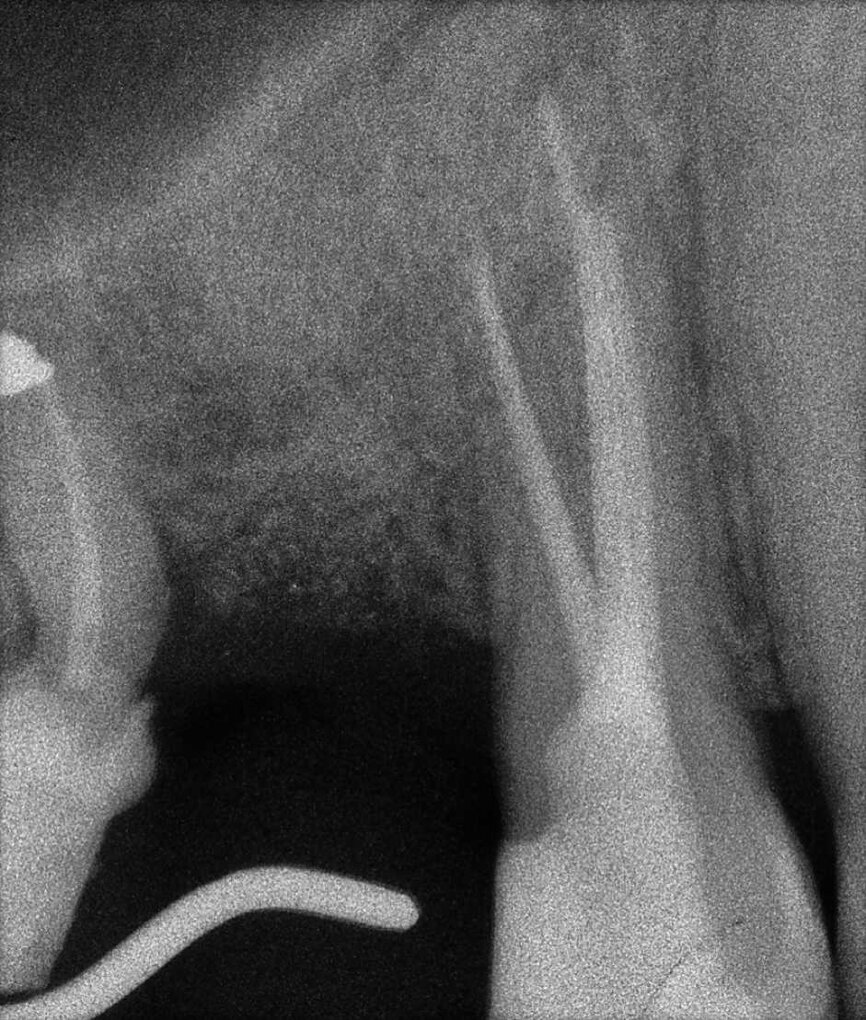

Il en va tout autrement pour la prémolaire mandibulaire présentée dans les figures 7 à 9 où, malgré l’absence de signes radiologiques de lésion et le traitement endodontique visiblement correct réalisé par un autre confrère, le patient se plaint d’une douleur persistante, qui est à la fois spontanée et déclenchée par un test de percussion de la dent. Dans ce cas, l’excellent traitement endocanalaire réalisé précédemment semble indiquer le besoin de recourir à une approche endodontique chirurgicale, susceptible de garantir un taux de réussite plus élevé que celui d’un simple retraitement. Étant donné le doute sur le diagnostic, nous avons décidé de réaliser un examen 3D et celui-ci révèle une lésion endodontique causée par un canal lingual resté sans traitement. Grâce à ce diagnostic exact, il devient possible d’envisager une intervention ciblée sur la pulpe restante, et de réaliser un traitement efficace du canal non traité.